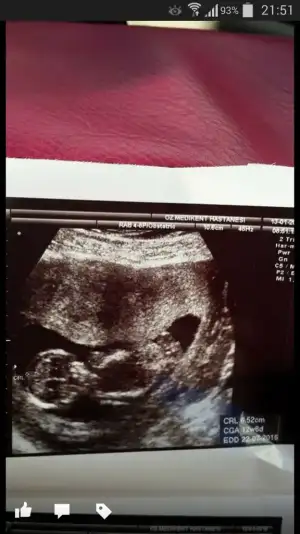

Tsk ederm cnm,bunda yanilma payi olmuyor degil mi?bariz belli kız olduğu. nub yan yatmış

Canım ilk fotografa bakmamıştım bebek tam yan değil hafif arkası dönük sidellanın tahmini doğru sanırım...Cnm bidaha baksana ya,sidella2011 nub yan yatmis kiz dedi..

Cnm bu en son foto 13+6, bunada baksana daha net bu foto..Canım ilk fotografa bakmamıştım bebek tam yan değil hafif arkası dönük sidellanın tahmini doğru sanırım...